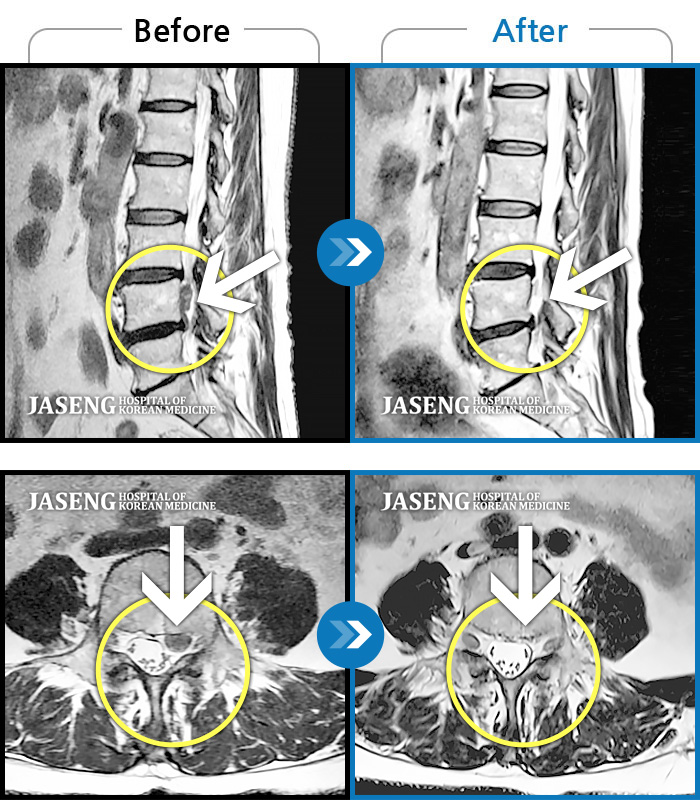

Before

After

환자에게 사전 동의를 받아 동일 조건에서 촬영되었습니다.

개인에 따라 치료 후 부작용이 발생할 수 있으니 의료진과 상담 후 치료를 진행하시기 바랍니다.

허리 중간부위 통증, 간헐적으로 양측 엉치 부위 저림

우측 허리 엉덩이부터 다리 당김, 통증